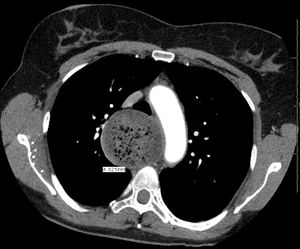

تعذر الارتخاء المريئي أو اللا ارتخائية أو الأكالازيا أو تشنج الفؤاد إنگليزية: Achalasia هو أحد أمراض خلل حركية المريء يفقد فيه المريء قدرته الطبيعية على القيام بحركات التمعج وتفشل المصرة المريئية السفلية في الارتخاء استجابة لعملية البلع.[1]

التشخيص